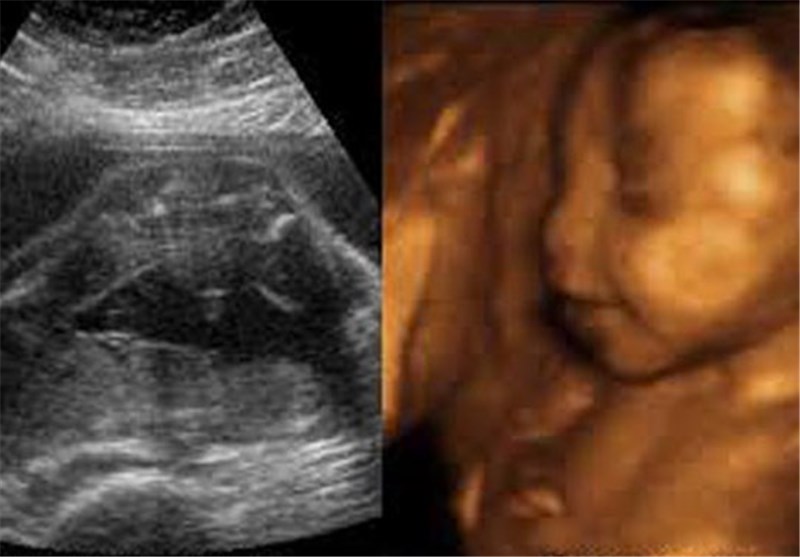

سونوگرافی‌های غیرضروری ولی اجباری/3 "نه" به نوعی غربالگری گران

رئیس انجمن علمی مامایی کشور انجام برخی سونوگرافی‌های سه بُعدی مربوط به سلامت جنین و تشخیص جنسیت را برای اکثر زنان باردار غیرضروری عنوان کرد و گفت: ورود اینگونه غربالگری در نظام سلامت کشور نه مقرون به صرفه، نه اثربخش و نه علمی است.

ناهید خداکرمی در گفت‌وگو با خبرنگار سلامت تسنیم، درباره رواج انجام سونوگرافی‌های سه بُعدی و غربالگری‌های مربوط به سلامت جنین و تشخیص جنسیت که بیشتر هم در مراکز خصوصی و بدون پوشش بیمه صورت می‌پذیرد، اظهار داشت: انجام اینگونه سونوگرافی‌ها برای اکثر زنان باردار ضرورتی ندارد، و نمی‌توان هزینه‌های هم برای اینگونه غربالگری‌ها در نظر گرفت در حالیکه اکثر نتایج این سونوگرافی‌ها نیز نُرمال است زیرا اگر یک رصدی از بخش خصوصی در طی چند سال اخیر صورت پذیرد که این غربالگری‌ها را انجام می‌دهند مشاهده می‌شود در بیش از 90 درصد موارد وضعیت نرمال و طبیعی است.

رئیس انجمن علمی مامایی کشور در پاسخ به این پرسش که به هر حال اینگونه سونوگرافی‌ها را متخصصان زنان و زایمان به زنان باردار توصیه می‌کنند، گفت: این فرهنگ درستی نبوده و نیست، بلکه به مادران در معرض خطر از جمله زنان بالای سن 35 سال، و یا دارای بیماری‌ زمینه‌ای؛ چنین غربالگری برای انجام اینگونه سونوگرافی‌ها باید توصیه شود.

ناهید خداکرمی ادامه داد: مشکلی که پیش آمده این است که زن باردار را وادار به انجام اینگونه سونوگرافی‌ها می‌کنند و لحن پیشنهاد به صورتی است که مادر فکر می‌کند که اگر این سونوگرافی را انجام ندهد دچار مشکل می‌شود.

رئیس انجمن علمی مامایی کشور با صحه گذاشتن به این مسئله که متخصصان زنان و زایمان؛ زن باردار را به انجام اینگونه سونوگرافی‌ها راغب می‌کنند، گفت: بنابراین ورود اینگونه غربالگری در نظام سلامت کشور که دولت بخواهد پول آن را بپردازد نه مقرون به صرفه، نه اثربخش و نه علمی است.

مراقبت‌های مادر توسط ماما بیمه نیست

خداکرمی خاطرنشان کرد: آن چیزی که ضروری است خدمات پایه ای سلامت است ولی هنوز مراقبت‌های مادر که ماما باید انجام دهد تحت پوشش بیمه نیست و چطور باید بیاییم و یک غربالگری گران را تحت پوشش قرار دهیم بنابراین بهتر است خدمات به مادران به صورت جامع تحت پوشش بیمه قرار گیرد.